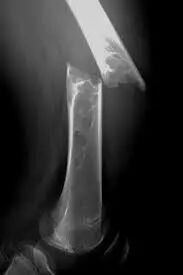

MM引起的病理性骨折

影像检查首选MRI或PET/CT

长期以来,X 线经济、简便,一直作为诊断 MM 骨质破坏和分期的重要标准,但它也有局限性。X 线检测溶骨性病变的敏感性很低,漏诊率较高,只有在骨小梁破坏超过 30% 时才能显示阳性,有约 20% 的 MM 患者在确诊时骨骼检查仍为阴性,所以 X 线现已不推荐用于 MM 骨病变检查。CT 的敏感性和分辨率较 X 线有明显提高,最主要缺点是辐射太大,且含碘对比剂有损肾功能,所以不常规推荐。

MRI 和 PET/CT 有较高准确性和敏感性,且在显示软组织、脊髓和髓外病变方面有更大优势,因此建议有条件的患者行 MRI 或 PET/CT 检查。当然,避免影像学误诊还需影像科医生结合患者临床资料,提高对 MM 的认识和警惕。